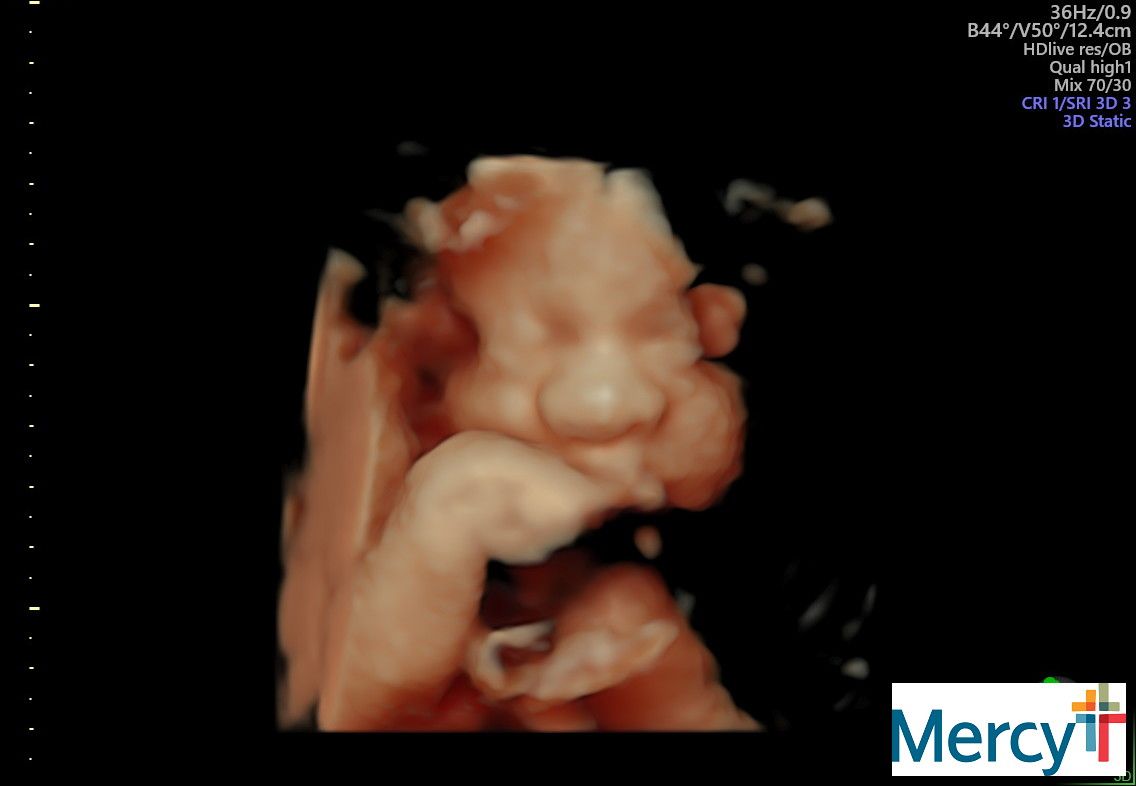

The belly is in full swing! Look at this face!